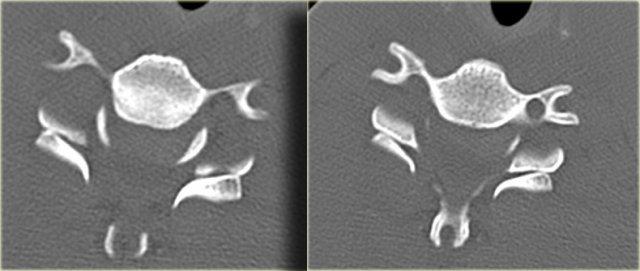

Trật khớp mặt một bên (2)

Trên hình axial, khớp mặt bên trái bình thường và hình dạng có nét tương đồng với chiếc hamburger.

Bên phải thấy dấu hiệu ‘hamburger lật ngược’ điển hình.